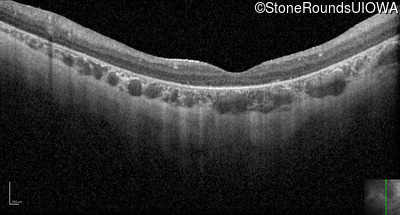

Optical Coherence Tomography - Right - 10/300 sc

Exemplar / OCT Stack